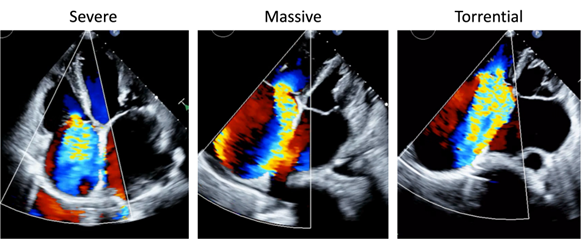

Despite these advances, the evaluation of TR severity remains a critical cornerstone of patient care. Traditionally, echocardiography has been the primary tool for grading TR, but conventional classifications were often limited to “mild, moderate, and severe.” This framework did not fully capture the wide clinical spectrum of disease, especially at the higher end. To address this gap, a new five-grade classification has recently been proposed and increasingly adopted: mild, moderate, severe, massive, and torrential TR. This extended classification allows clinicians to better stratify patients, to appreciate the incremental risk associated with extreme TR, and to define more appropriate thresholds for intervention. In daily practice, however, applying this new classification requires both knowledge and caution. Echocardiographic parameters such as vena contracta width, effective regurgitant orifice area, and regurgitant volume must be carefully integrated with supportive signs, including right atrial and ventricular remodeling, hepatic vein flow reversal, and inferior vena cava dilatation. In this session, we will focus on these practical issues. We will highlight the clinical significance of the five-grade system (figure), illustrate how it has already influenced patient selection for emerging transcatheter therapies, and discuss its impact on daily decision-making. In addition, we will address potential pitfalls, including over- or underestimation of severity, and emphasize the importance of integrating clinical context, right ventricular function, and patient symptoms alongside echocardiographic grading.